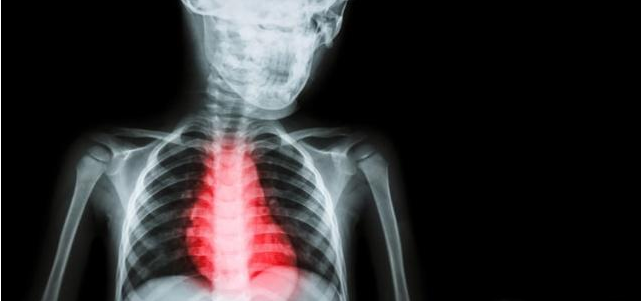

心脏病作为常见疾病 , 相信很多人都知道 。 但是 , 当你的身体发出这样信号的时候 , 你是否知道你的心脏已经出现问题了呢?那么 , 究竟有心脏疾病的人常会出现哪些症状呢?下面由小编给大家科普一下吧 。

2. 容易出现胸闷、胸痛现象

如果经常性出现胸闷、胸痛 , 每次这种情况持续时间长 , 甚至出现剧烈疼痛的状况 , 很大可能会出现心绞痛甚至急性心肌梗死 , 这个时候你就要警惕啦 , 应该立即就诊看医 。